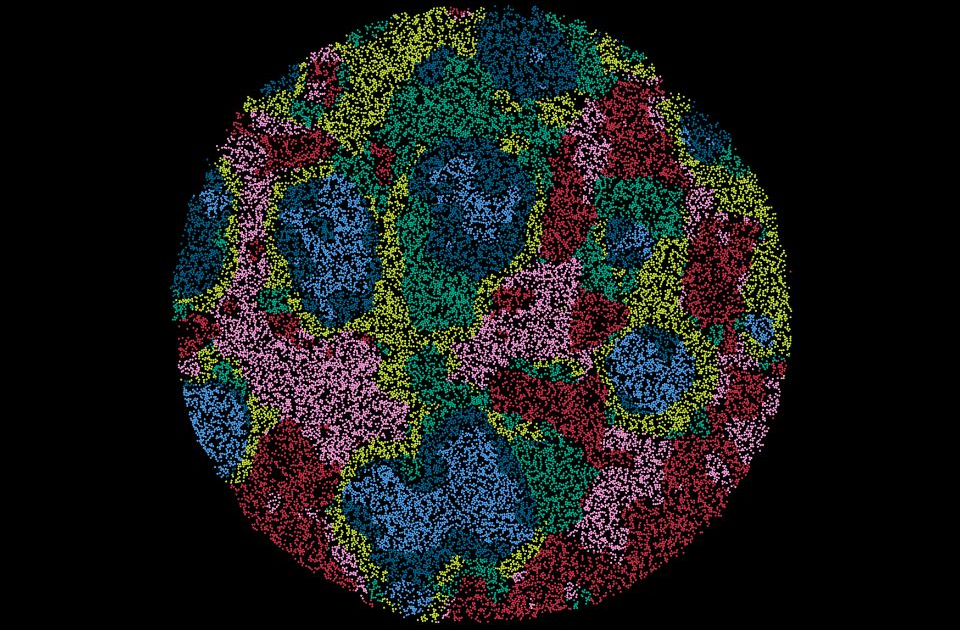

Un team di ricercatori, guidato dal professore associato Ashraful Haque dell’Università di Melbourne e capo del laboratorio del Doherty Institute, ha utilizzato una tecnica avanzata chiamata trascrittomica spaziale, nota anche come genomica tissutale, per creare mappe dettagliate del tessuto della milza durante l’infezione da malaria. Questa tecnologia ha permesso loro di scoprire dove si trovano i diversi tipi di cellule e come interagiscono, fornendo preziose informazioni sui loro ruoli e meccanismi.

Hanno osservato che le cellule che combattono le infezioni tendono a raggrupparsi in aree specifiche della milza, vicino ad altre cellule immunitarie dove lavorano insieme per avviare un’efficace risposta immunitaria contro il parassita della malaria.